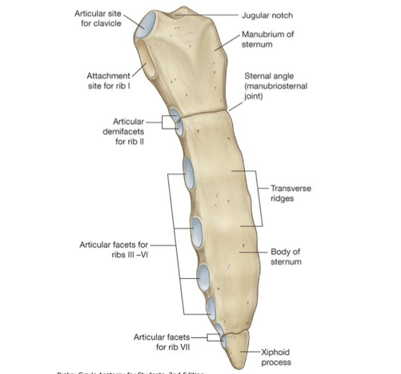

Identify the structures of the sternum

- Manubrium

- Sternum (body)

- Sternal angle

- Jugular notch

- Articular sites for clavicle

- Xiphoid

M up top

Body in middle

X point at bottom

jugular notch at top

two facets next to that is articulation sites for the clavicle

- Jugular (sternal) notch (JN)

- Sternal angle (SA)